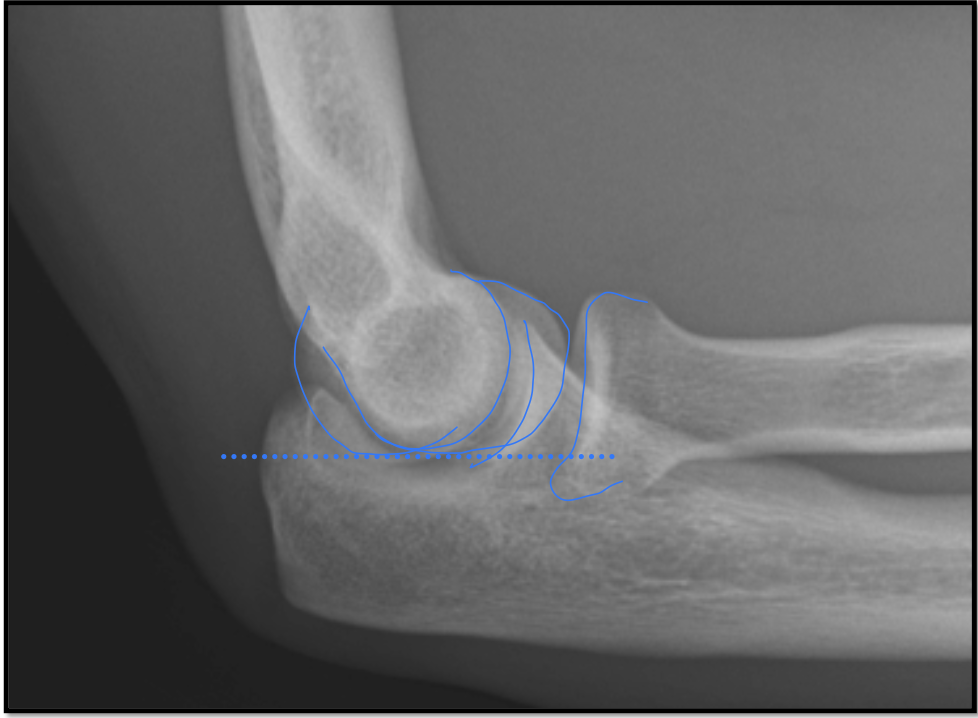

Lateral Elbow Criteria

• elbow flexed 90

• capitulum and trochlea superimposed

• articulating surfaces of the radial head and coronoid process are aligned